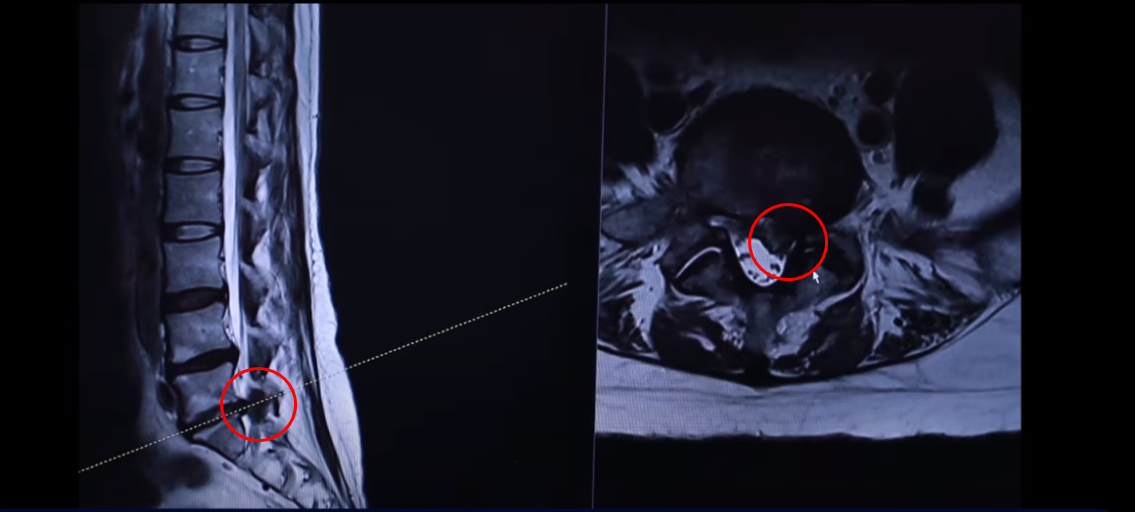

43세 여자 허리 디스크 파열 환자분 MRI 보도록 하겠습니다. 이분은 파열이 어마어마하게 심합니다. 세 마디에 퇴행성 디스크가 있는데 5번 1번을 보면 위와 아래로 밀려 올라가 있죠.

터져서 밀려나온 디스크 수핵이 위와 아래로 밀려 나가 있습니다. 보시면 이쪽이 왼쪽입니다. 환자의 왼쪽을 완전히 덮어버렸죠.

다시 동생분 MRI로 돌아가겠습니다. 언니분하고 똑같이 이 동생분 세 마디 디스크가 퇴행돼 있죠 그리고 마지막 마디가 터져서 이렇게 왼쪽으로 심하게 밀려 나가 있습니다.

언니분보다 터진 정도는 더 심합니다. 그래서 이렇게 디스크가 심하게 파열되고 또 마비 증상까지 있는 분들 이런 분들은 이 환자분이 들으신 것처럼 정형외과나 신경외과에서 즉시 수술을 해야 된다. 또 마비 증상까지 있으니까 바로 수술을 하지 않으면 마비 증상이 오래되면 신경이 심하게 눌려 있으면 신경 기능이 많이 떨어지면 만약 마비가 풀리지 않는다고 그러면 그건 이제 장애가 되는 거죠. 그렇기 때문에 즉시 수술을 해야 된다 이렇게 듣는데 이렇게 파열이 심한 분들일수록 저희는 오히려 비수술 재활 치료가 성공할 확률이 더 높다. 역설적이게도 파열이 심하면 심할수록 치료가 더 잘될 확률이 높다. 저희 모커리한방병원이 이렇게 설명을 하고 있는데 왜 그럴까요?